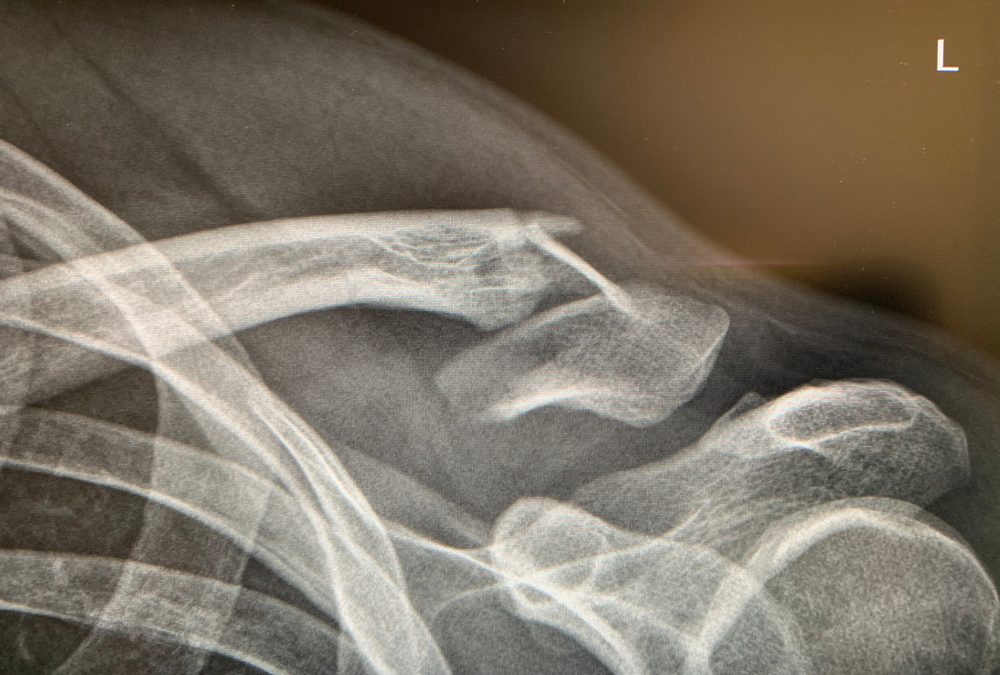

Missed fractures in radiography

When a fracture is suspected the first point of call is the x-ray department. Unfortunately, one of the main causes of diagnostic error is failing to interpret x-ray images correctly. Minor fractures can be mistaken for old injuries or appear within normal parameters. The choice of imaging type is important in identifying fractures. If the wrong type of imaging is ordered, if the images are of inadequate quality, the wrong part of the skeleton or incomplete views are taken this may result in a missed diagnosis.

Subtle fractures

Some more subtle fractures such as stress or hairline fractures may have no discernible symptoms or signs of fracture and this makes them more difficult to detect. This is often a problem when the bone has a thin outer layer ( cortex) such as the scaphoid or talus where a fracture may not be visible in the acute phase. Sometimes they can be mistaken for sprains.

Patients’ complex anatomy

Certain anatomical structures for example in the small bones of the hands or feet can make it more difficult to identify fractures. In a patient who has had previous fractures or soft tissue injuries, fractures may not initially be discernible. If the Emergency Medicine clinician has any doubt about the images they should ask a radiologist to examine the images taken of patients with a complex anatomy or previous complications before the patient is discharged from the Emergency Department. They may suggest further imaging to prevent a fracture being missed.